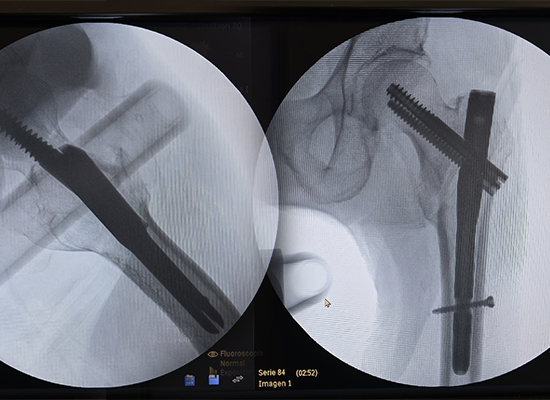

Postoperative X-ray showing Intertan Intramedullary Nail fixation of left intertrochanteric fracture, Peru

During the surgery, Dr. Rivera noted that the CZMEDITECH Intertan Intramedullary Nail provided superior biomechanical stability and smooth implantation.

Dual cephalocervical screws enhanced rotational resistance

Improved axial compression across the fracture line

Stable fixation minimizing risks of varus collapse

Even force distribution promoting bone healing

The tapered and polished nail tip allowed the implant to glide through the medullary canal with minimal resistance, reducing tissue trauma.

After fixation, the patient began early assisted mobilization. Pain was significantly relieved, limb alignment was restored, and follow-up radiographs confirmed stable implant positioning with signs of progressive fracture healing.